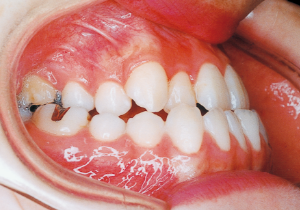

Age at Initial Visit: 8 years 1 month, Female / Protruding lower bite. Protruding lower jaw

1 Initial Visit 8-29-’79

Although there were many missing deciduous teeth, the number of permanent teeth was not problematic (4). The amount of negative overjet was significant (1). On cephalometric radiographs, the mandibular ramus was not relatively long, but the large gonial angle and the long mandibular body were noticeable, indicating an overall tendency of the mandible to project inferiorly and anteriorly. High lower facial height was also characteristic.

A potential predisposition to mandibular protrusion was clearly evident.